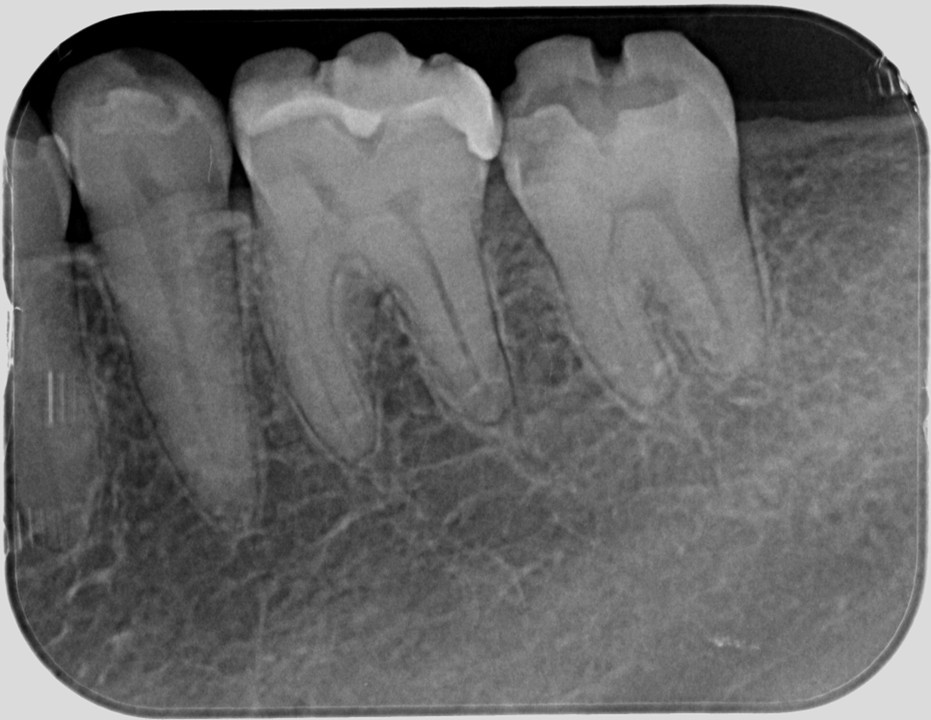

臨床例「直接覆髄法」を用いた一症例(図6)

術前レントゲン

髄角付近までう蝕が進行していることが確認できる

(図12)術直後のレントゲン像

近心髄角に一部MTAと思われる不透過像を認める

術後7年以上経過して状態は安定している(図13)。

術後7年との比較 左:2017.11.09 右:2024.11.23

近心髄角付近にはデンチィンブリッジ形成による象牙質様の不透過像の生成が確認できる